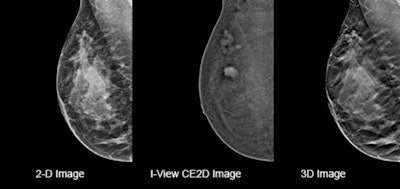

Data from clinical trials support this. DBT has been shown to detect up to 65% more invasive cancers than a 2D mammogram alone.1 Additionally, the Tomosynthesis plus Synthesized Mammography (TOSYMA) study found that DBT plus synthesized mammography detected 3.5 times more invasive cancers than digital mammography alone in the first screening round.2 Moreover, by administering a similar radiation dose during DBT as in 2D mammography,3 we can simultaneously capture a 3D and a 2D image.

Clinical images comparing results from the same patient taken on a 2D mammography system (left), using contrast-enhanced software (center), and on a 3D mammography gantry (right). Figure courtesy of Hologic.